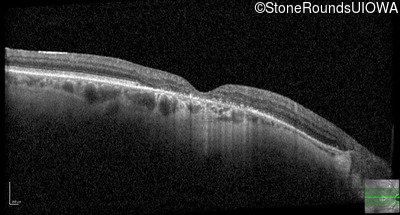

This 52 year old man had normal vision until his mid 30's when he began to have trouble distinguishing colors. the issuing 10 years he had a gradual loss of visual acuity accompanied by increasing photophobia.

| Age at visit: 55 years |

| Age at visit: 58 years |

| Age at visit: 61 years |

| Age at visit: 64 years |